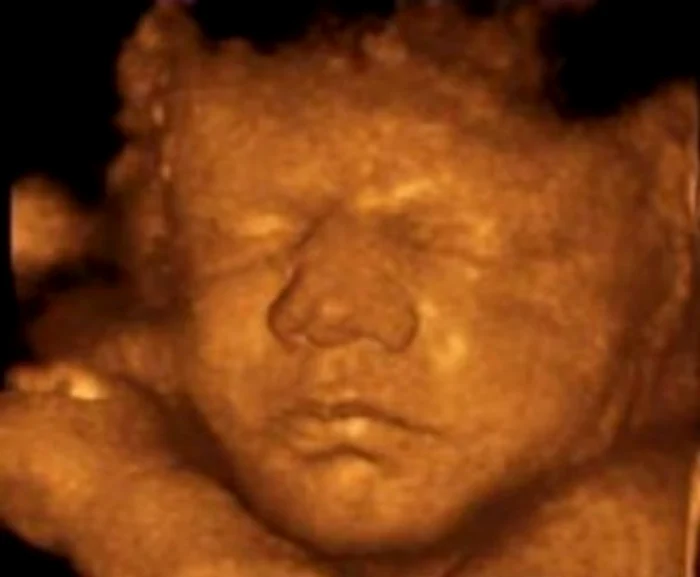

Cercetătorii de la Universităţile Durham şi Lancaster, Marea Britanie, au studiat ecografiile 4D ale copiilor nenăscuţi şi au observat că aceştia simulează expresii faciale care exprimă durerea.

Studiile pe ecografii arată că expresiile faciale ale unui copil aflat în burtică pot fi de mai multe feluri. De la simple zâmbete până la încruntări complexe ale feţei, care implică jocuri de sprâncene, nas şi buze.

În cadrul studiului au fost scanate ecografiile 4D şi filmările în care au apărut opt fetiţe nenăscute şi şapte copii nenăscuţi, de sex masculin.